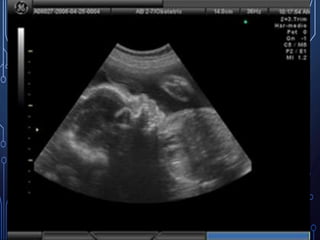

• Sombra fetal en USG

USG